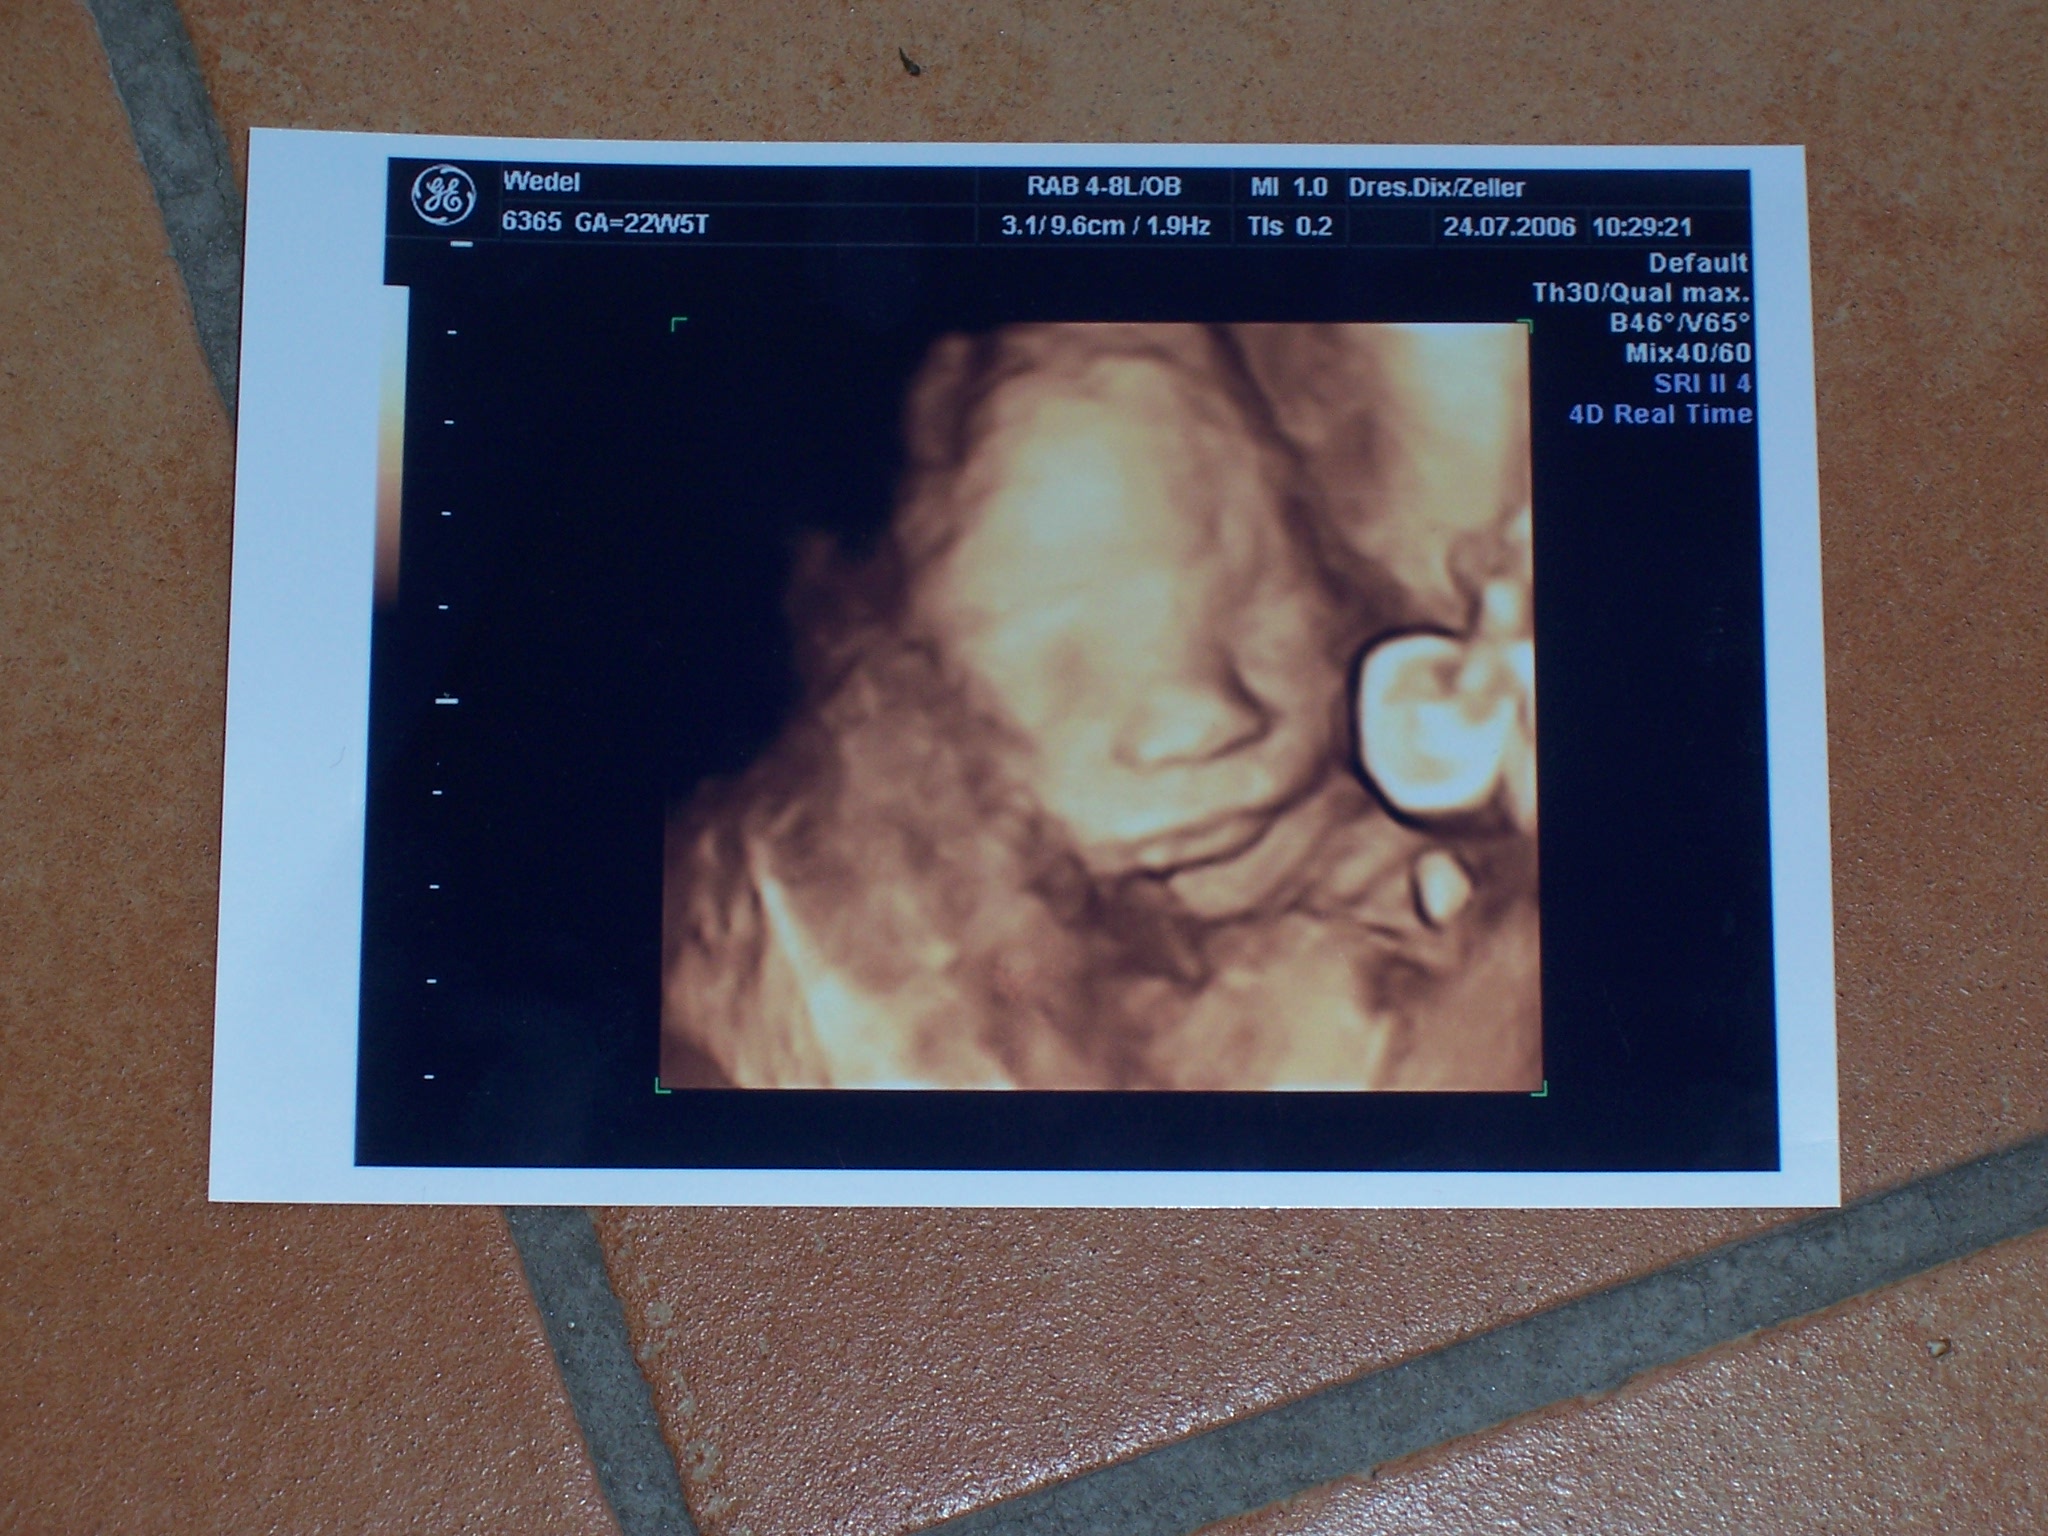

Wir hatten gestern wieder US. Die große Überraschung war, dass meine Ärztin jetzt einen 3 D US hat. Das war toll

Wir haben auch ein 100 % Outing bekommen. Es ist doch ein Junge

Ich stelle euch gleich noch Fotos ein. Auf dem einen ist der absolute Beweis drauf